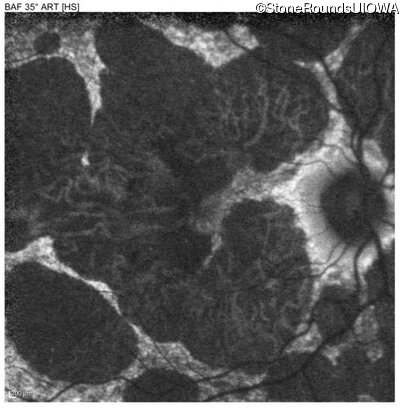

Blue Autofluorescence - Left - 20/40 +1

Exemplar